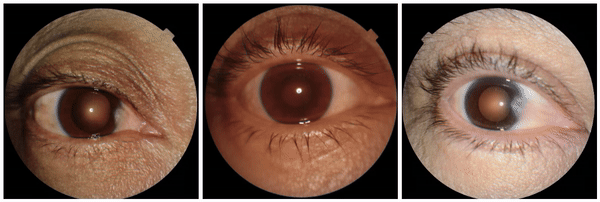

Similarly, when examining the previously published research that AI models can identify race based on radiology images, one feature appeared related to the clavicle (collar bone) angle/position. This attribute is also seen when taking the CXR from different angles: posterior-anterior (PA, taken for outpatients standing up) versus anterior-posterior (AP, taken for patients on a hospital bed). In this dataset, we verified that the ratio of self-reported race differed for PA versus AP images with a directionality consistent with the observed attribute. This association may be due to a mix of factors including dataset gathering processes, healthcare access, or patient population aspects.

StylEx-5-Confounders

Examples of an apparent inferior displacement of the clavicles, associated with self-reported race. Animations are presented as a flickering between 2 frames to accentuate the difference.